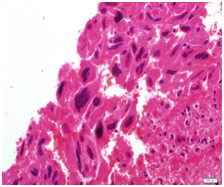

A specimen labeled as left frontoparietal hematoma - ? cavernoma from a 41 year old non-hypertensive female patient on ventilator was received for histopathologic examination. The patient was transferred from outside hospital to neurosurgical department of our hospital for craniotomy and evacuation of intracerebral hematoma. The clinoradiologic diagnosis was spontaneous intracerebral hematoma with intraventricular extension with normal ventricle, probably due to cavernoma. The microscopic examination of the specimen revealed extensive hemorrhage with peripherally placed mono-nucleated and multinucleated atypical cells. The mononucleotide cells were medium to large size with abundant cytoplasm and central large hyperchromatic nuclei. The multinucleated cells were large with abundant eosinophilic cytoplasm and hyperchromatic multinucleated bizarre nuclei. They were considered as cytotrophoblasts and syncytiotrophoblasts respectively (Figure 1-4). Immunohistochemistry showed that the atypical cells were CKAE1AE3 +, HCG+, GFAP-, CD31- and Vimentin- (Figure 5 to 10). A thin rim of GFAP positive glial tissue was seen in one fragment. Based on these findings, a diagnosis of metastatic choriocarcinoma was made. The patient survived the surgery and started recovering neurologically, but chose to go back to her own country for further management. So, we could not get any details of her obstetric history or previous medical illness.

Figure 2 Syncytiotophoblasts.

Figure 4 Syncytiotophoblasts.